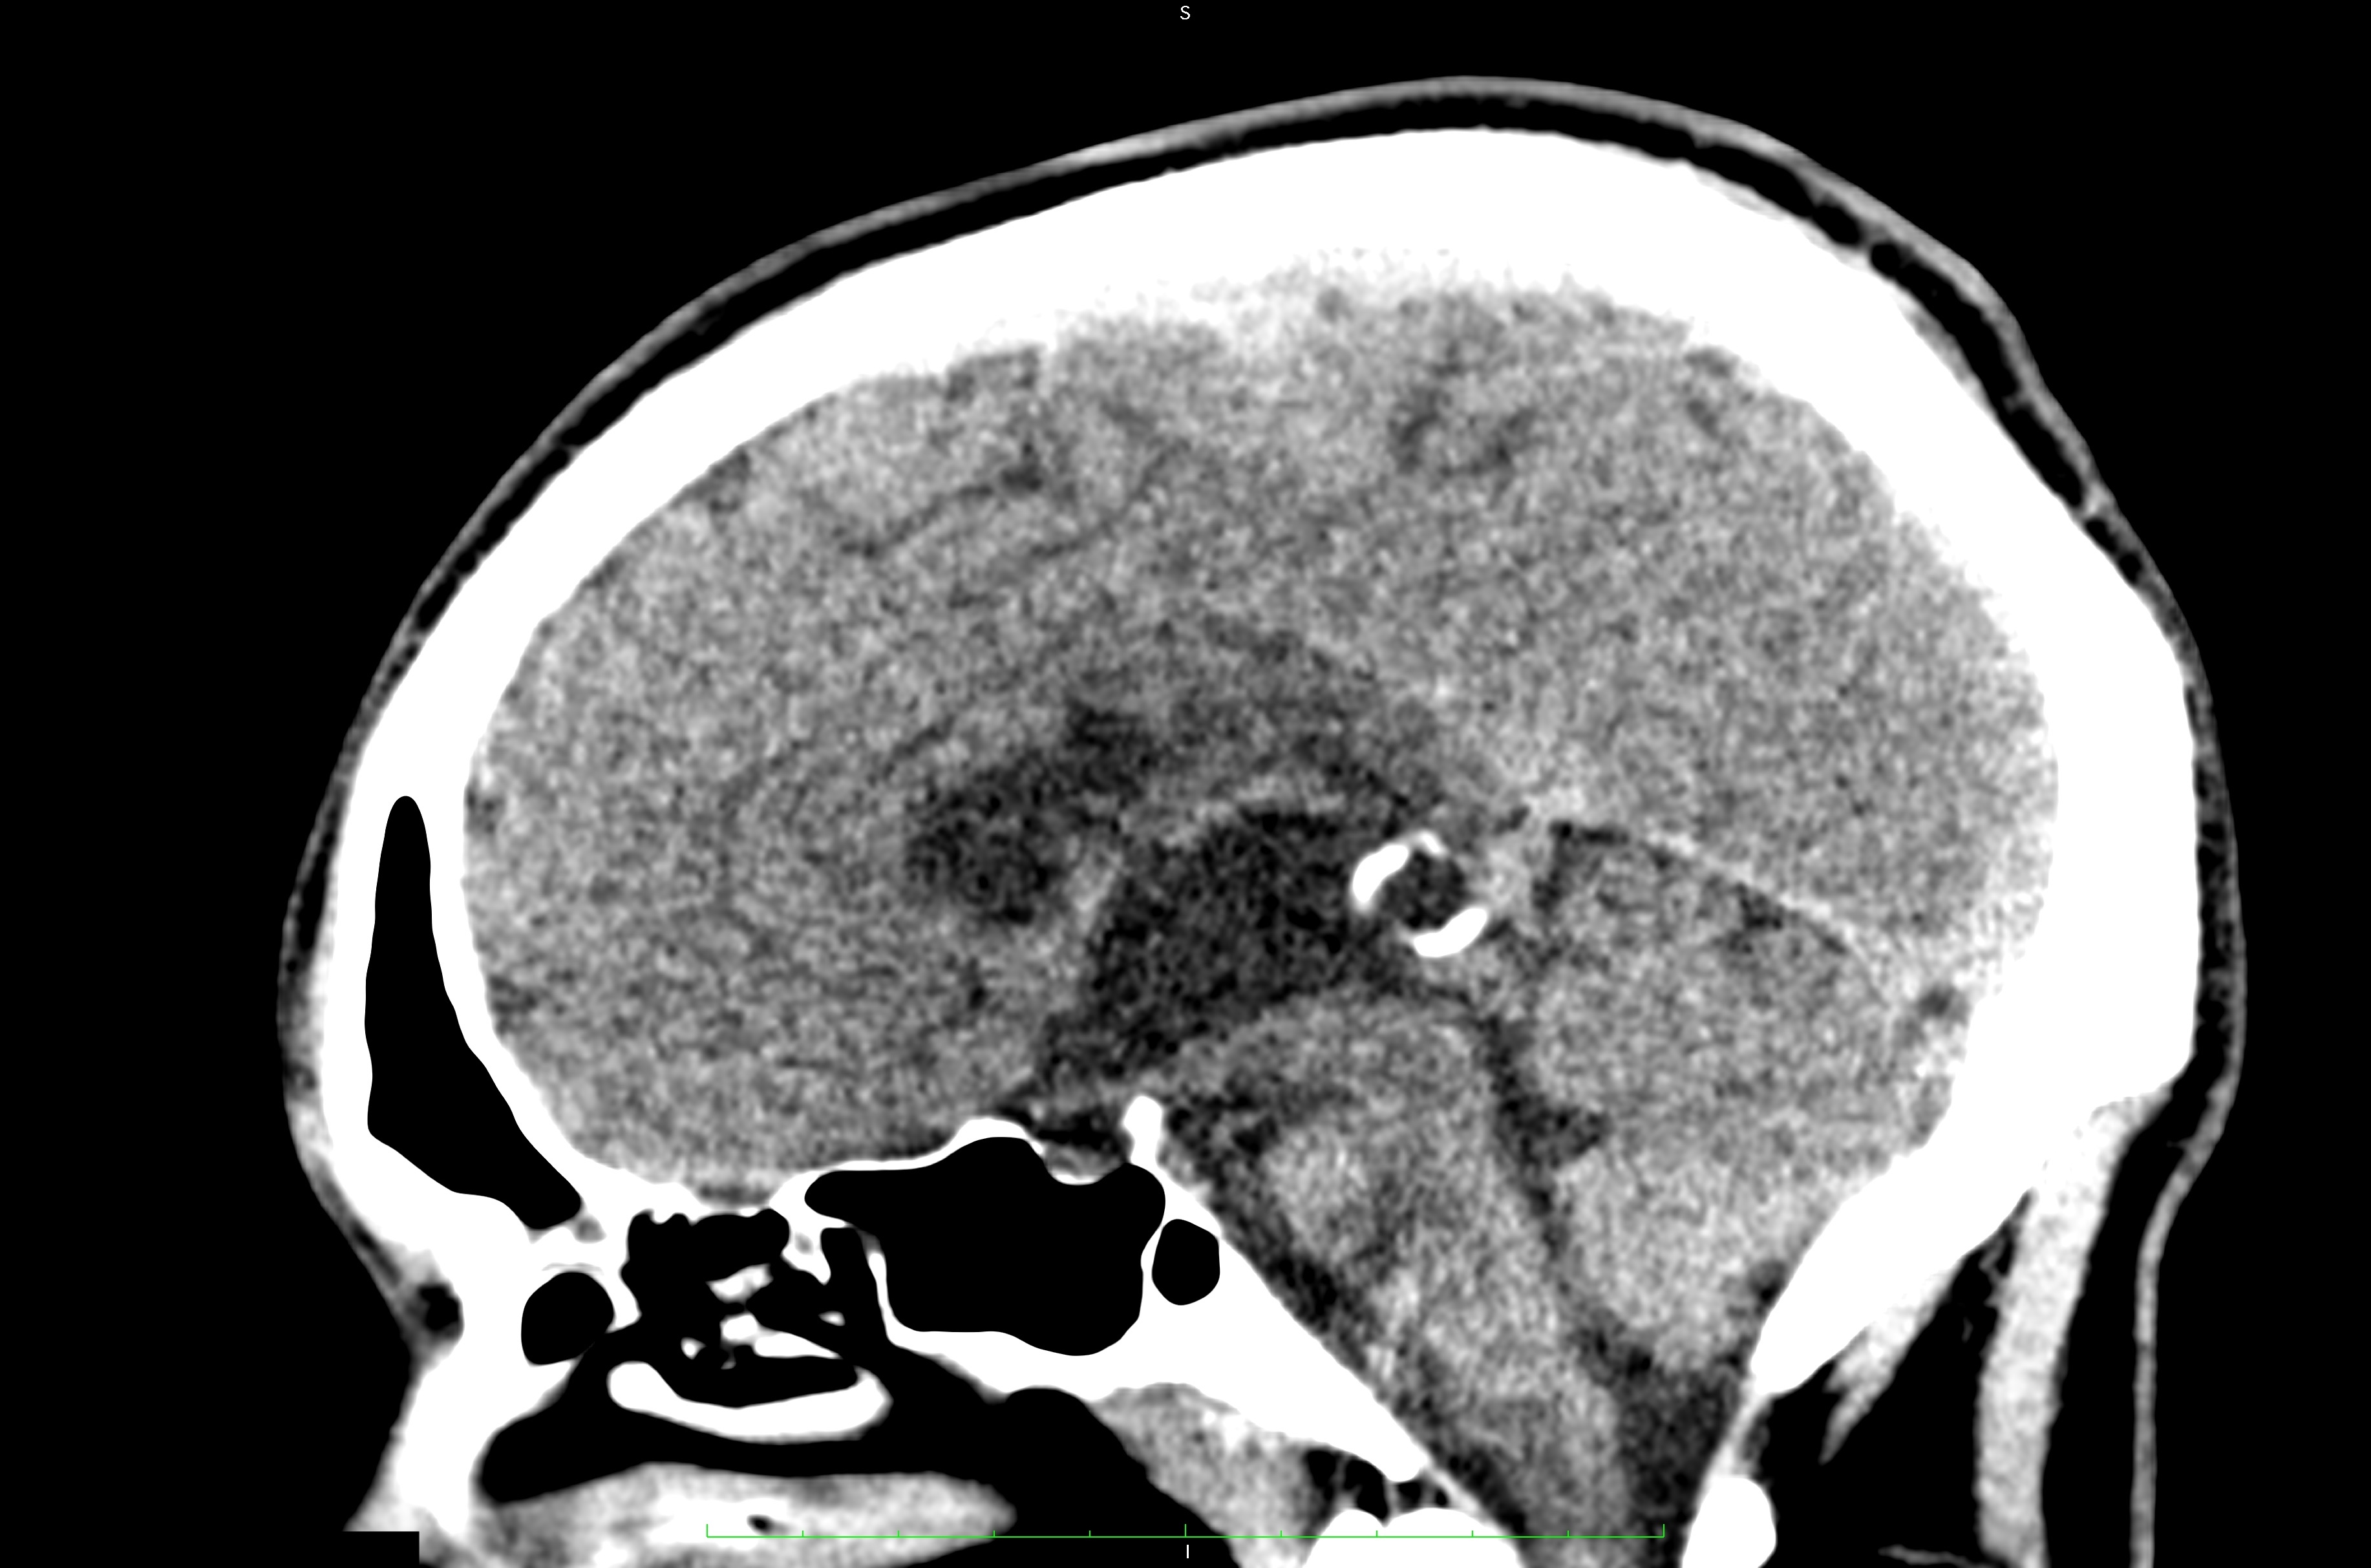

Pathologies of the pineal gland region are frequently encountered in daily neurosurgical practice. It is important to remember that, besides usually asymptomatic pineal gland cysts, neoplasms of a different origin may also occur in this region. The rarity of the most dangerous lesions – pineal gland apoplexy and pineal tumors – might cause problems with proper diagnosis and treatment. Their occurrence is commonly associated with symptomatic hydrocephalus caused by aqueductal stenosis. Currently, in such cases, endoscopic procedures, including endoscopic third ventriculostomy (ETV), are commonly and widely chosen as treatment options. Endoscopic procedures not only enable decompression of hydrocephalus but also further diagnosis of its cause. Herein, we present 3 case reports of endoscopic treatment with ETV performed in patients with hydrocephalus related to pineal region pathologies.